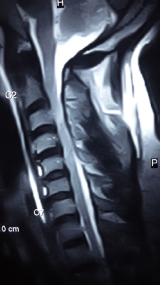

Investigations revealed normal haemogram and serum electrolytes. Plain radiograph of the skull was normal, while spinal radiographs revealed loss of normal cervical lordosis. No fracture or dislocation was seen. Spinal magnetic resonance imaging (MRI) showed generalized loss of disc signal intensities and posterior bulges. Marked canal stenosis at C3 vertebral level. There is also mildly increased parenchymal spinal cord intensity at this level and focal blooming artifacts (Figure 2). Features of hemorrhagic contusion at C3/C4 disc segment in a background Grade III degenerative disc disease and canal stenosis.

Figure 2 Spinal magnetic resonance imaging (MRI) showes generalized loss of disc signal intensities and posterior bulges.